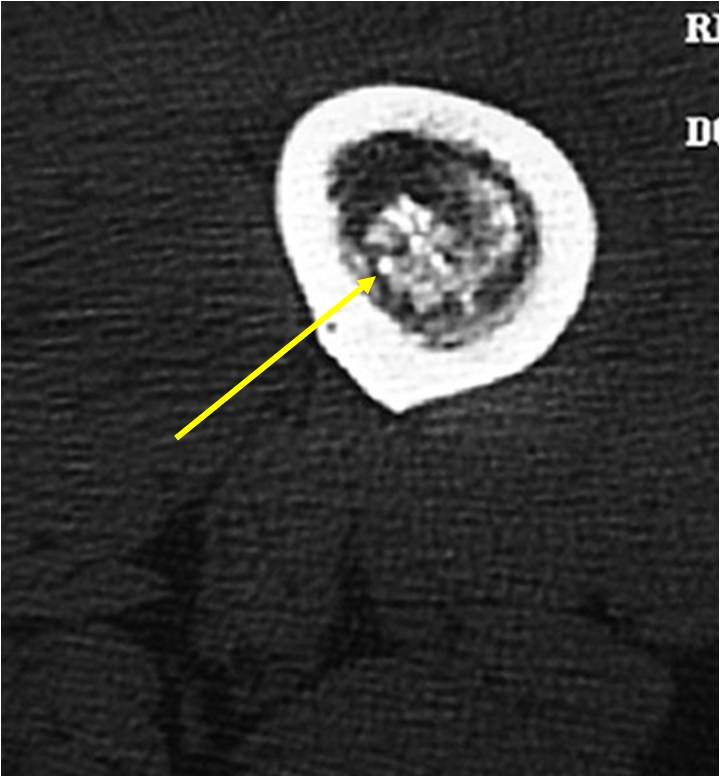

- MRI

- Lobulated margin

- Marked increased intensity long TR images

- Calcified chondroid – low intensity all sequences

MRI:

- Lobulated margin (Lobular Growth Pattern)

- T1 Weighted Images: Intermediate Signal Intensity

- Calcifications will be low signal

- T2 Weighted Images: High Signal Intensity

- High water content shows as high signal on T2 weighted images

- Calcifications will be low signal

- Marked increased intensity long TR images

- Calcified chondroid – low intensity all sequences

- There should never be any cortical destruction nor a soft tissue component. If this exists then the tumor must be a chondrosarcoma.

- Endosteal scalloping and cortical expansion is acceptable for phalangeal tumors. In most benign long bone cartilage tumors there is minimal endosteal scalloping but there should be no cortical expansion nor thickening. There should be no cortical destruction and no soft tissue component associated with an enchondroma. Cortical destruction, periosteal thickening, cortical expansion and a soft tissue component indicates a chondrosarcoma of the long bone.